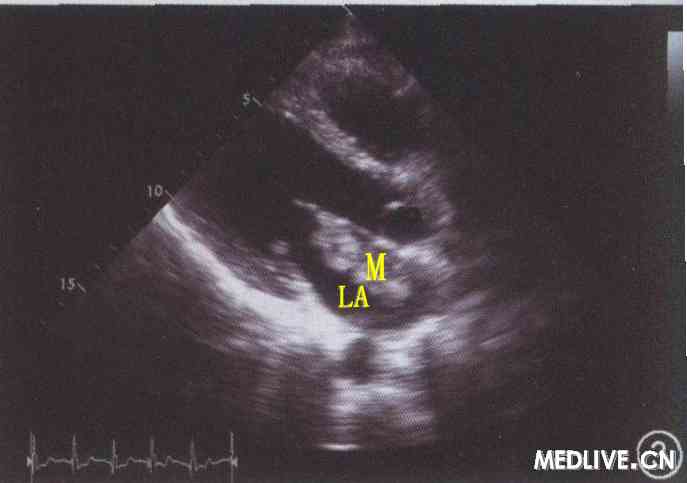

心脏彩色超声检查:显示心脏位置、形态、结构及各房室腔大小均正常;左心房内见偏强回声团,约2.1 cm×3.5 cm大小,以0.6 cm细蒂附着于房间隔中部,随心腔血流摆动。提示:左心房内实性占位性病变,黏液瘤可能性大(图3);左心功能正常。

图3左眼动脉阻塞患者心脏彩色超声图像,显示左心房内黏液瘤,LA示左心房,M示黏液瘤